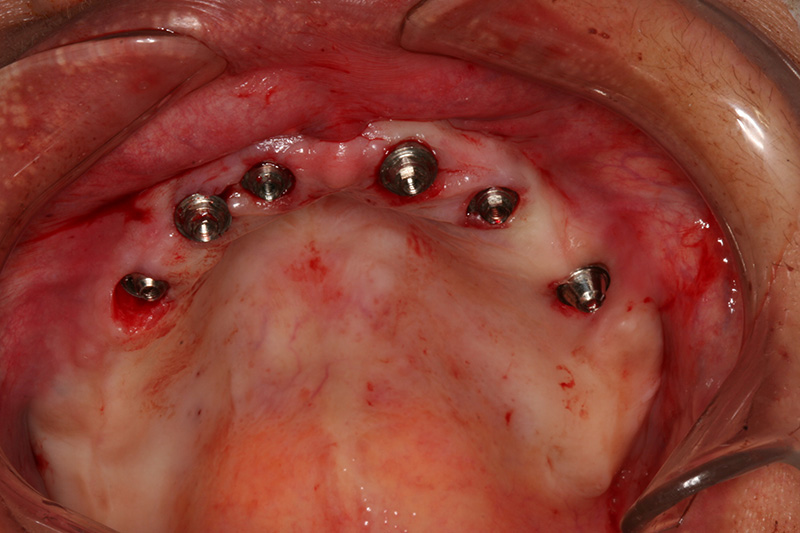

Na Clínica Pontes Odontologia, somos referência em implantes dentários em Fortaleza, oferecendo tratamentos de alta qualidade e tecnologia de ponta. Os implantes dentários são estruturas de titânio posicionadas cirurgicamente no osso maxilar ou mandibular para substituir as raízes dos dentes ausentes. Essa técnica permite a fixação de próteses personalizadas, restaurando a função mastigatória, a estética e a autoestima dos nossos pacientes.